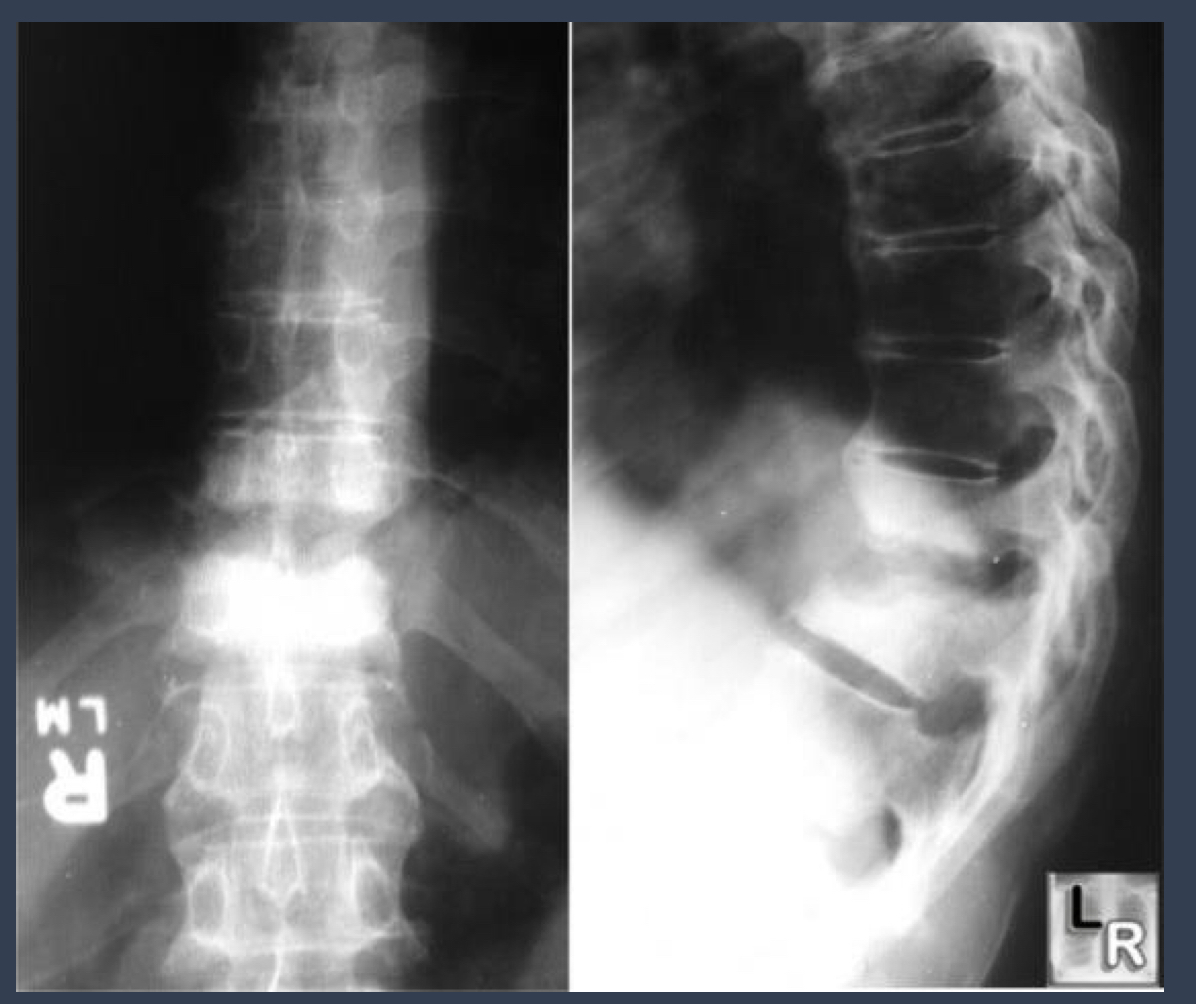

what kind of deformity is this?

what kind of disease is this?

gibbus deformity

a form of structural kyphosis found typically in upper lumbar and lower throacic vertebra where 1+ adjacent vertebrae become wedged. most offten develops in children as a result of spinal TB and is the result of collapse of vertebral bodies.

pott disease

form of TB that occurs outside lungs and seen in vertebra

slower than pyogenic spondylitis. lower thoracic and upper lumbar. begins at endplate. disc space loss is the earliest radiographic sign. lytic destruction 2-5 months.